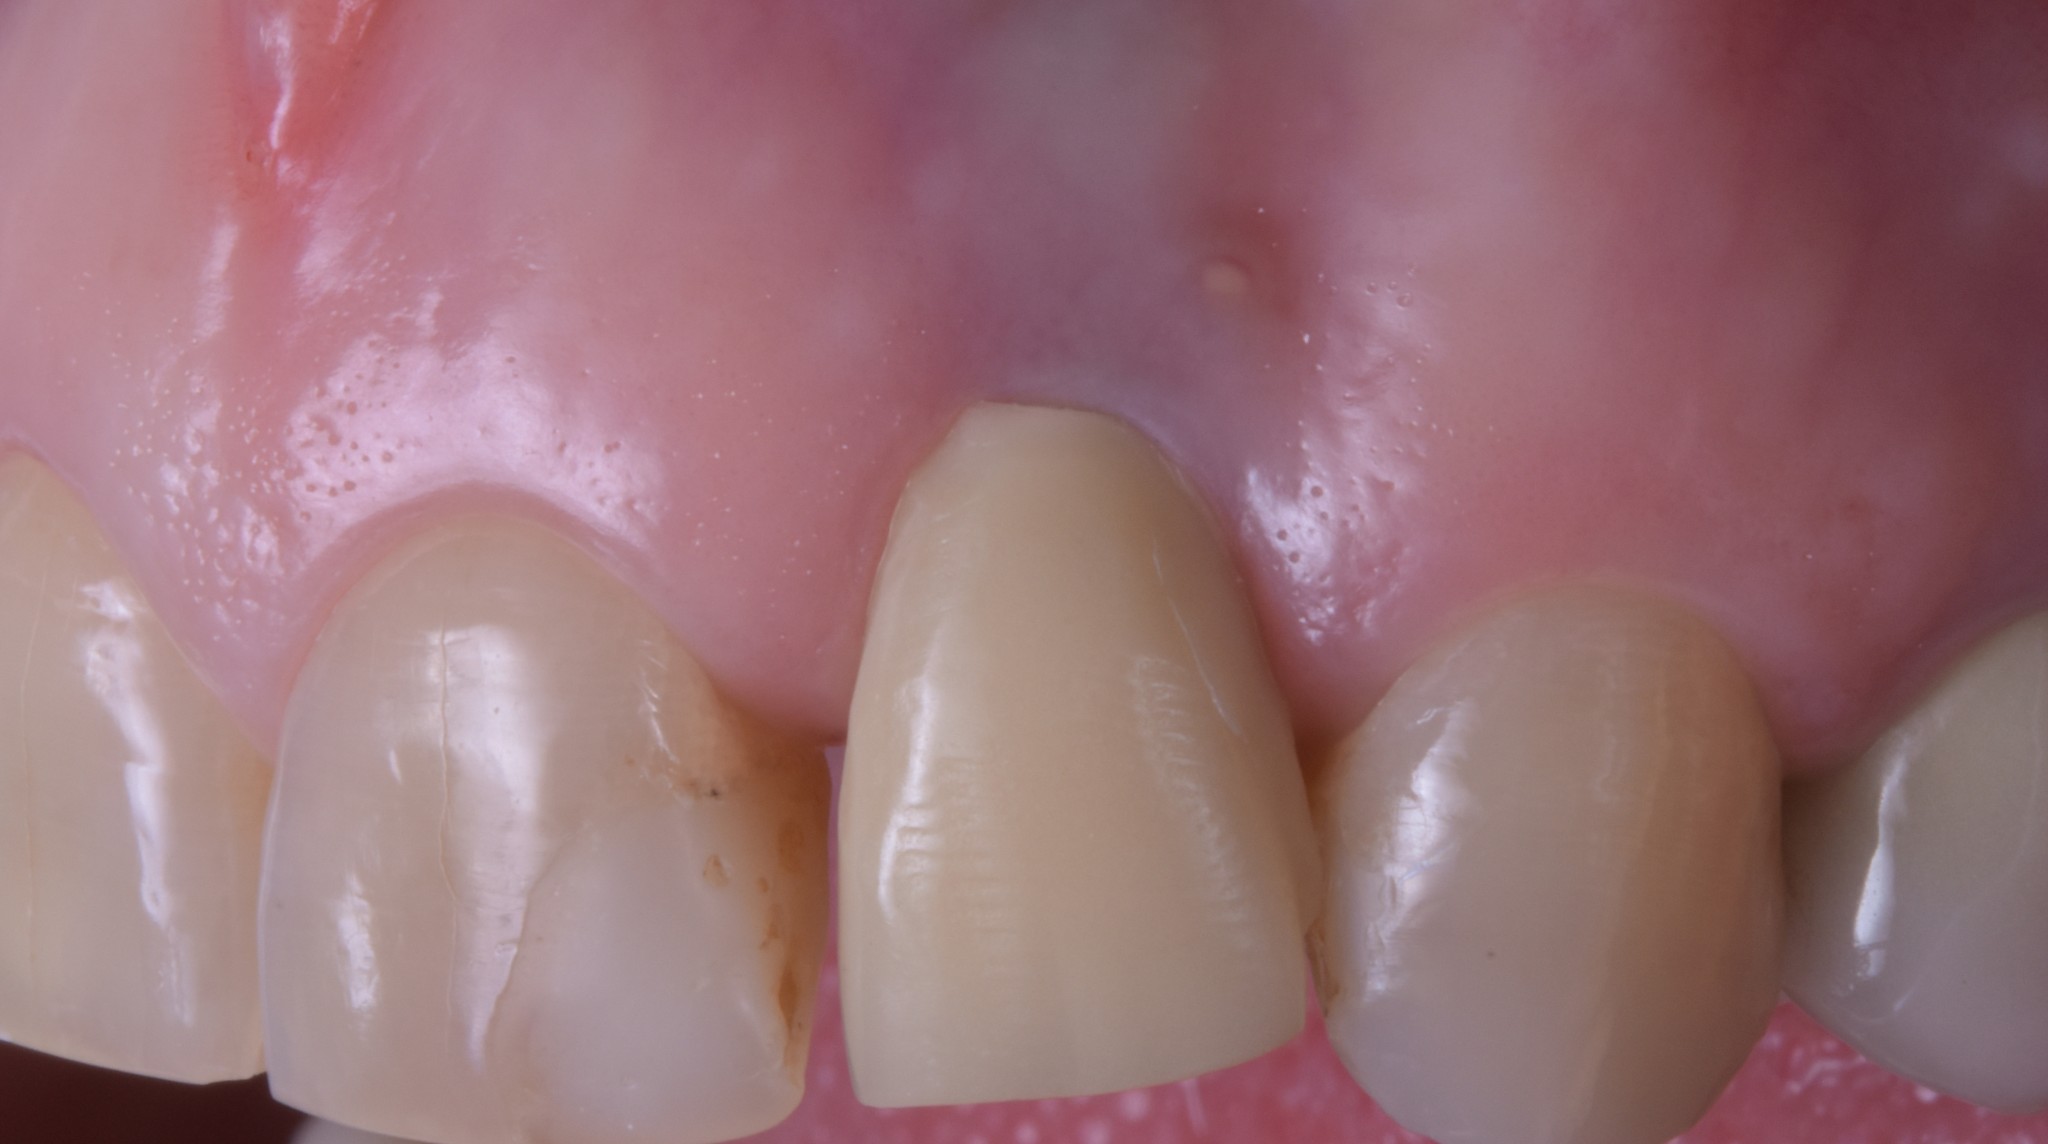

All’esame obiettivo si evidenziano:

- Fistola in sede vestibolare all’elemento 2.2 supportato da impianto

- Risultato estetico… (chiedo scusa ma qui devo tornare me stesso) di merda!

E non mi si venga a raccontare la storiella del “tu non puoi giudicare perché non sai quale fosse la complessità del caso” perché fino ad un anno fa in quella sede la paziente aveva il suo dente che è stato tolto e sostituito con un impianto perché si era decementata una vecchia corona e l’elemento era stato giudicato irrecuperabile da punto di vista conservativo. Quindi è stato fatto un impianto post-estrattivo di un dente con parodonto sano. Posso affermare con ottimo grado di certezza che le cose difficili sono altre!!

Ecco qua caro Lodovico, un impianto che mastica ottimamente, con una buona salute dell’osso di supporto (dopo ti spiego da cosa era causata la fistola), che riempie egregiamente il “buco” lasciato dall’estrazione ma con UNA GESTIONE DEI TESSUTI MOLLI DRAMMATICAMENTE PESSIMA!